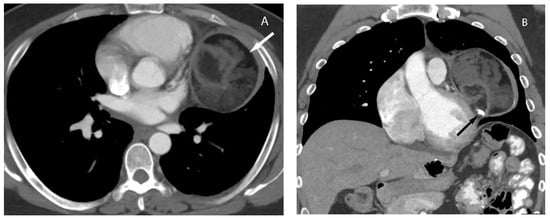

7. Germ Cell Tumors

9. Hypervascular Lesions